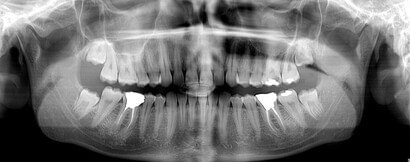

رادیوگرافی پانورکس (OPG)

رادیوگرافی پانورکس یا (OPG) نوعی تصویربرداری دو‌بعدی از کل فک، دندان‌ها، مفاصل فک و ساختارهای اطراف است. این تصویر به‌صورت یک نمای پانورامیک (سراسرنما) گرفته می‌شود و تمام دندان‌ها و فک را در یک عکس نشان می‌دهد.